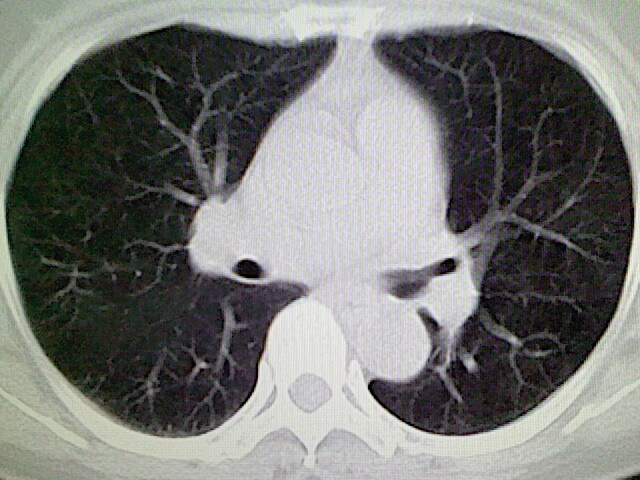

女,52岁,咳嗽,咳痰多日

左下肺陈旧纤维索条!

左肺舌段炎性改变

我见过几例,为炎症后纤维条索

慢性炎症后改变

考虑慢性炎性病灶粘连牵拉改变。

左肺舌叶纤维锁条病变。

左肺上叶下舌段炎症并局部胸膜反应。

左肺舌叶纤维索条影。

左肺舌叶段陈旧性病变

左肺舌段炎性反应。片子的质量太不好了。

左肺舌段炎性

炎性改变

左肺舌叶纤维索条影